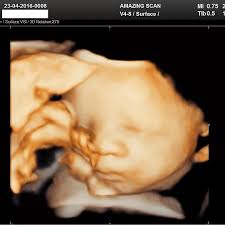

It excites them to see their unborn baby movements.

Ultrasound scans are the highlight of the pregnancy, it is taken at any intervals during the pregnancy period.

Moreover, it enables the mother to see the priceless view of their baby’s cutest reactions like yawning, smiling inside the womb.